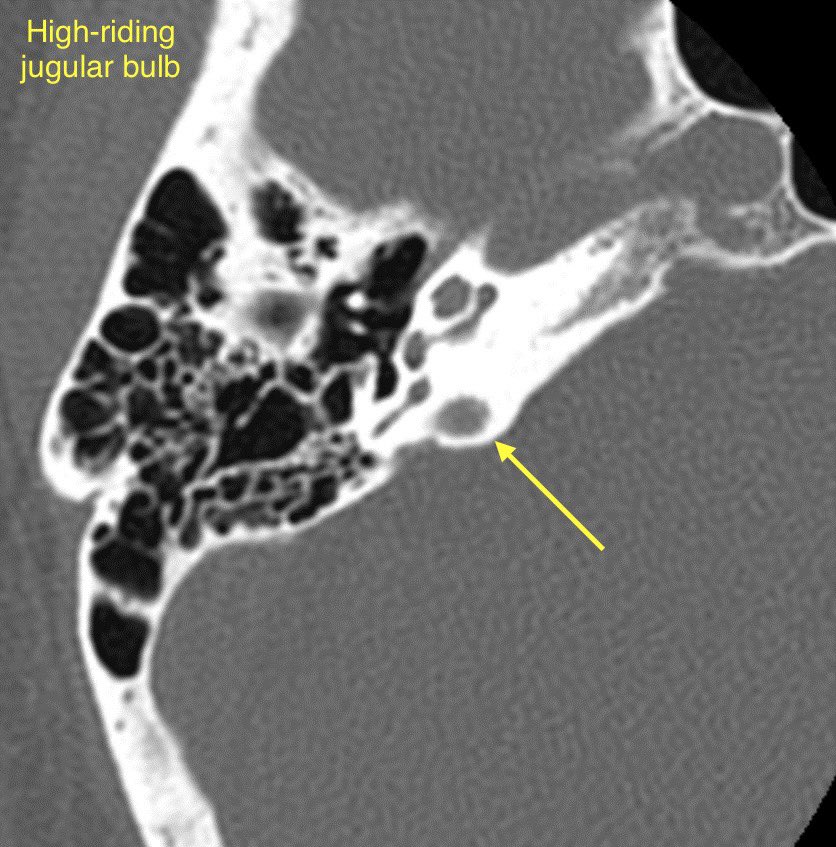

🔷JUGULAR BULB ABNORMALITIES

1️⃣High-riding jugular bulb

2️⃣Jugular bulb dehiscence

3️⃣Jugular bulb diverticulum

🔹High-riding jugular bulb is associated with jugular bulb dehiscence

💡"High" = within 2mm of the floor of the IAC, above the lower border of the round window, above the posterior semicircular canal, or above the basal turn of the cochlea

🔹Jugular bulb dehiscence: Thinning or visible defect of the jugular plate

🔹Jugular bulb diverticulum is a round outpouching arising from the jugular bulb and usually projects superomedially into the petrous bone